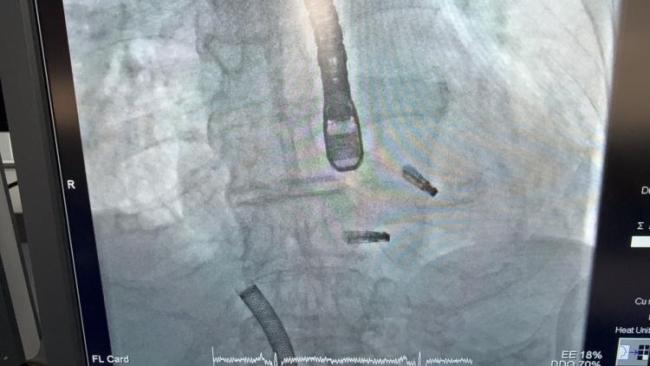

近日,上海市东方医院结构性心脏病中心何奔教授团队成功完成沪上首例二、三尖瓣“一站式”经皮介入微创修复手术,不用开胸,一次微创介入,同时修复两组瓣膜,将这位高龄高危患者从死亡警报中拉回。

84岁的李老先生,数月前因胸闷不适来到上海市东方医院,诊断为“急性冠脉综合征、非ST段抬高心肌梗死”。冠脉造影发现回旋支近段完全闭塞,医生紧急为他植入支架,成功开通血管。当时的心脏超声已显示他有“中重度二尖瓣反流、重度三尖瓣反流”,但考虑到他刚做完支架手术,医生希望先通过规范的药物治疗来稳定瓣膜反流情况,再评估是否需要介入干预。